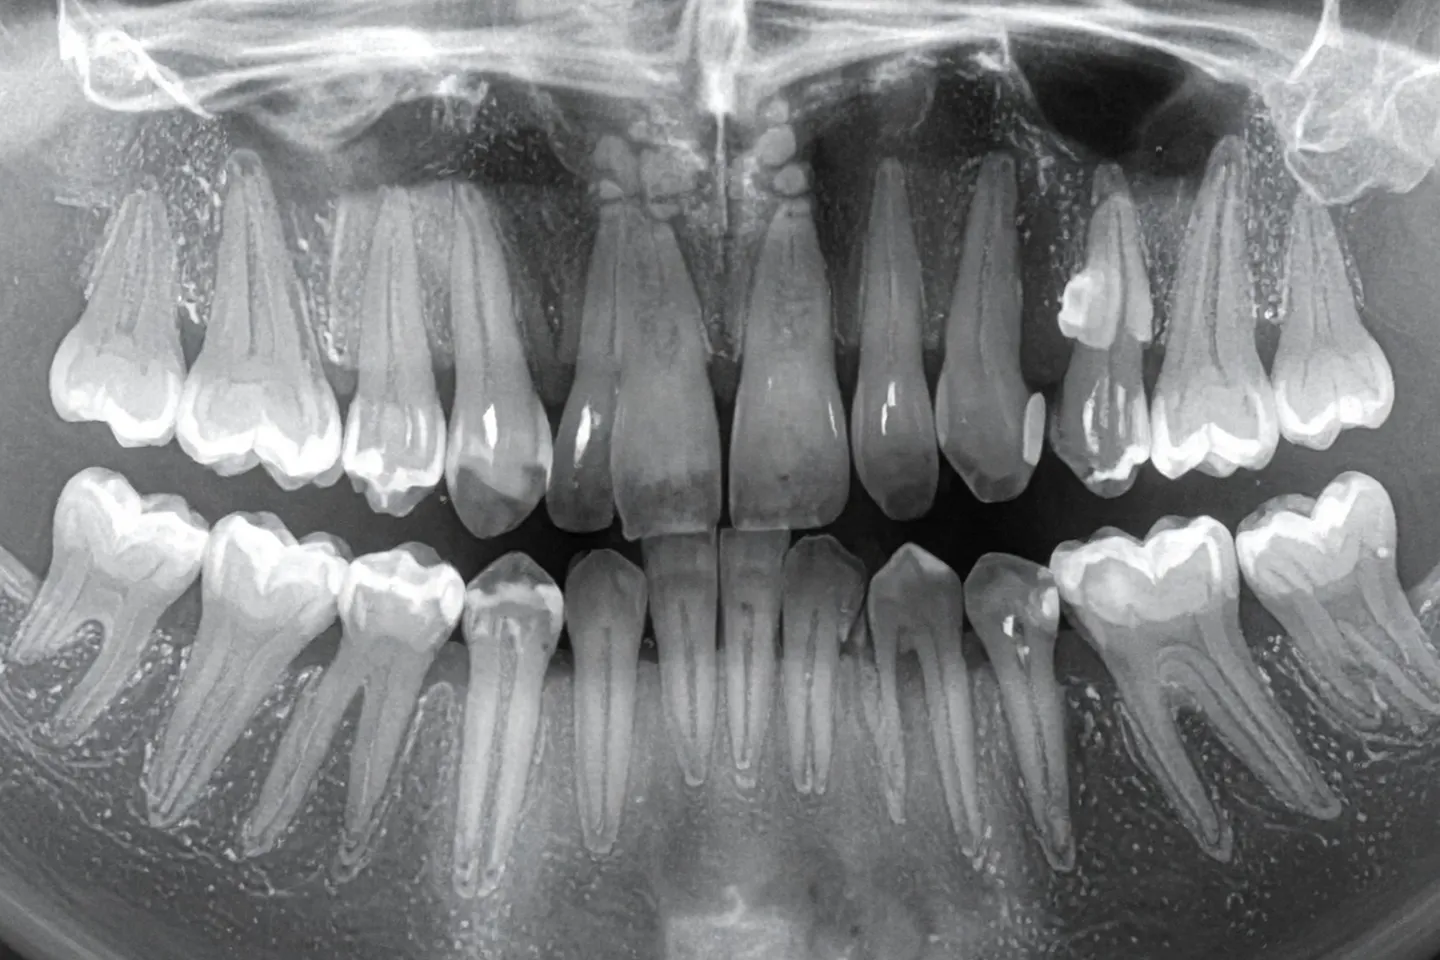

When a young permanent tooth is damaged due to trauma or decay before its root has fully developed, it’s called an immature tooth. These teeth have open root tips and thin, fragile walls, making them vulnerable to fracture and infection. At The Endodontic Office, we offer specialised treatments to preserve and strengthen these teeth while allowing natural root development to continue.

A: Root development can take several months. During this time, we monitor healing with periodic X-rays and adjust the treatment plan if necessary.